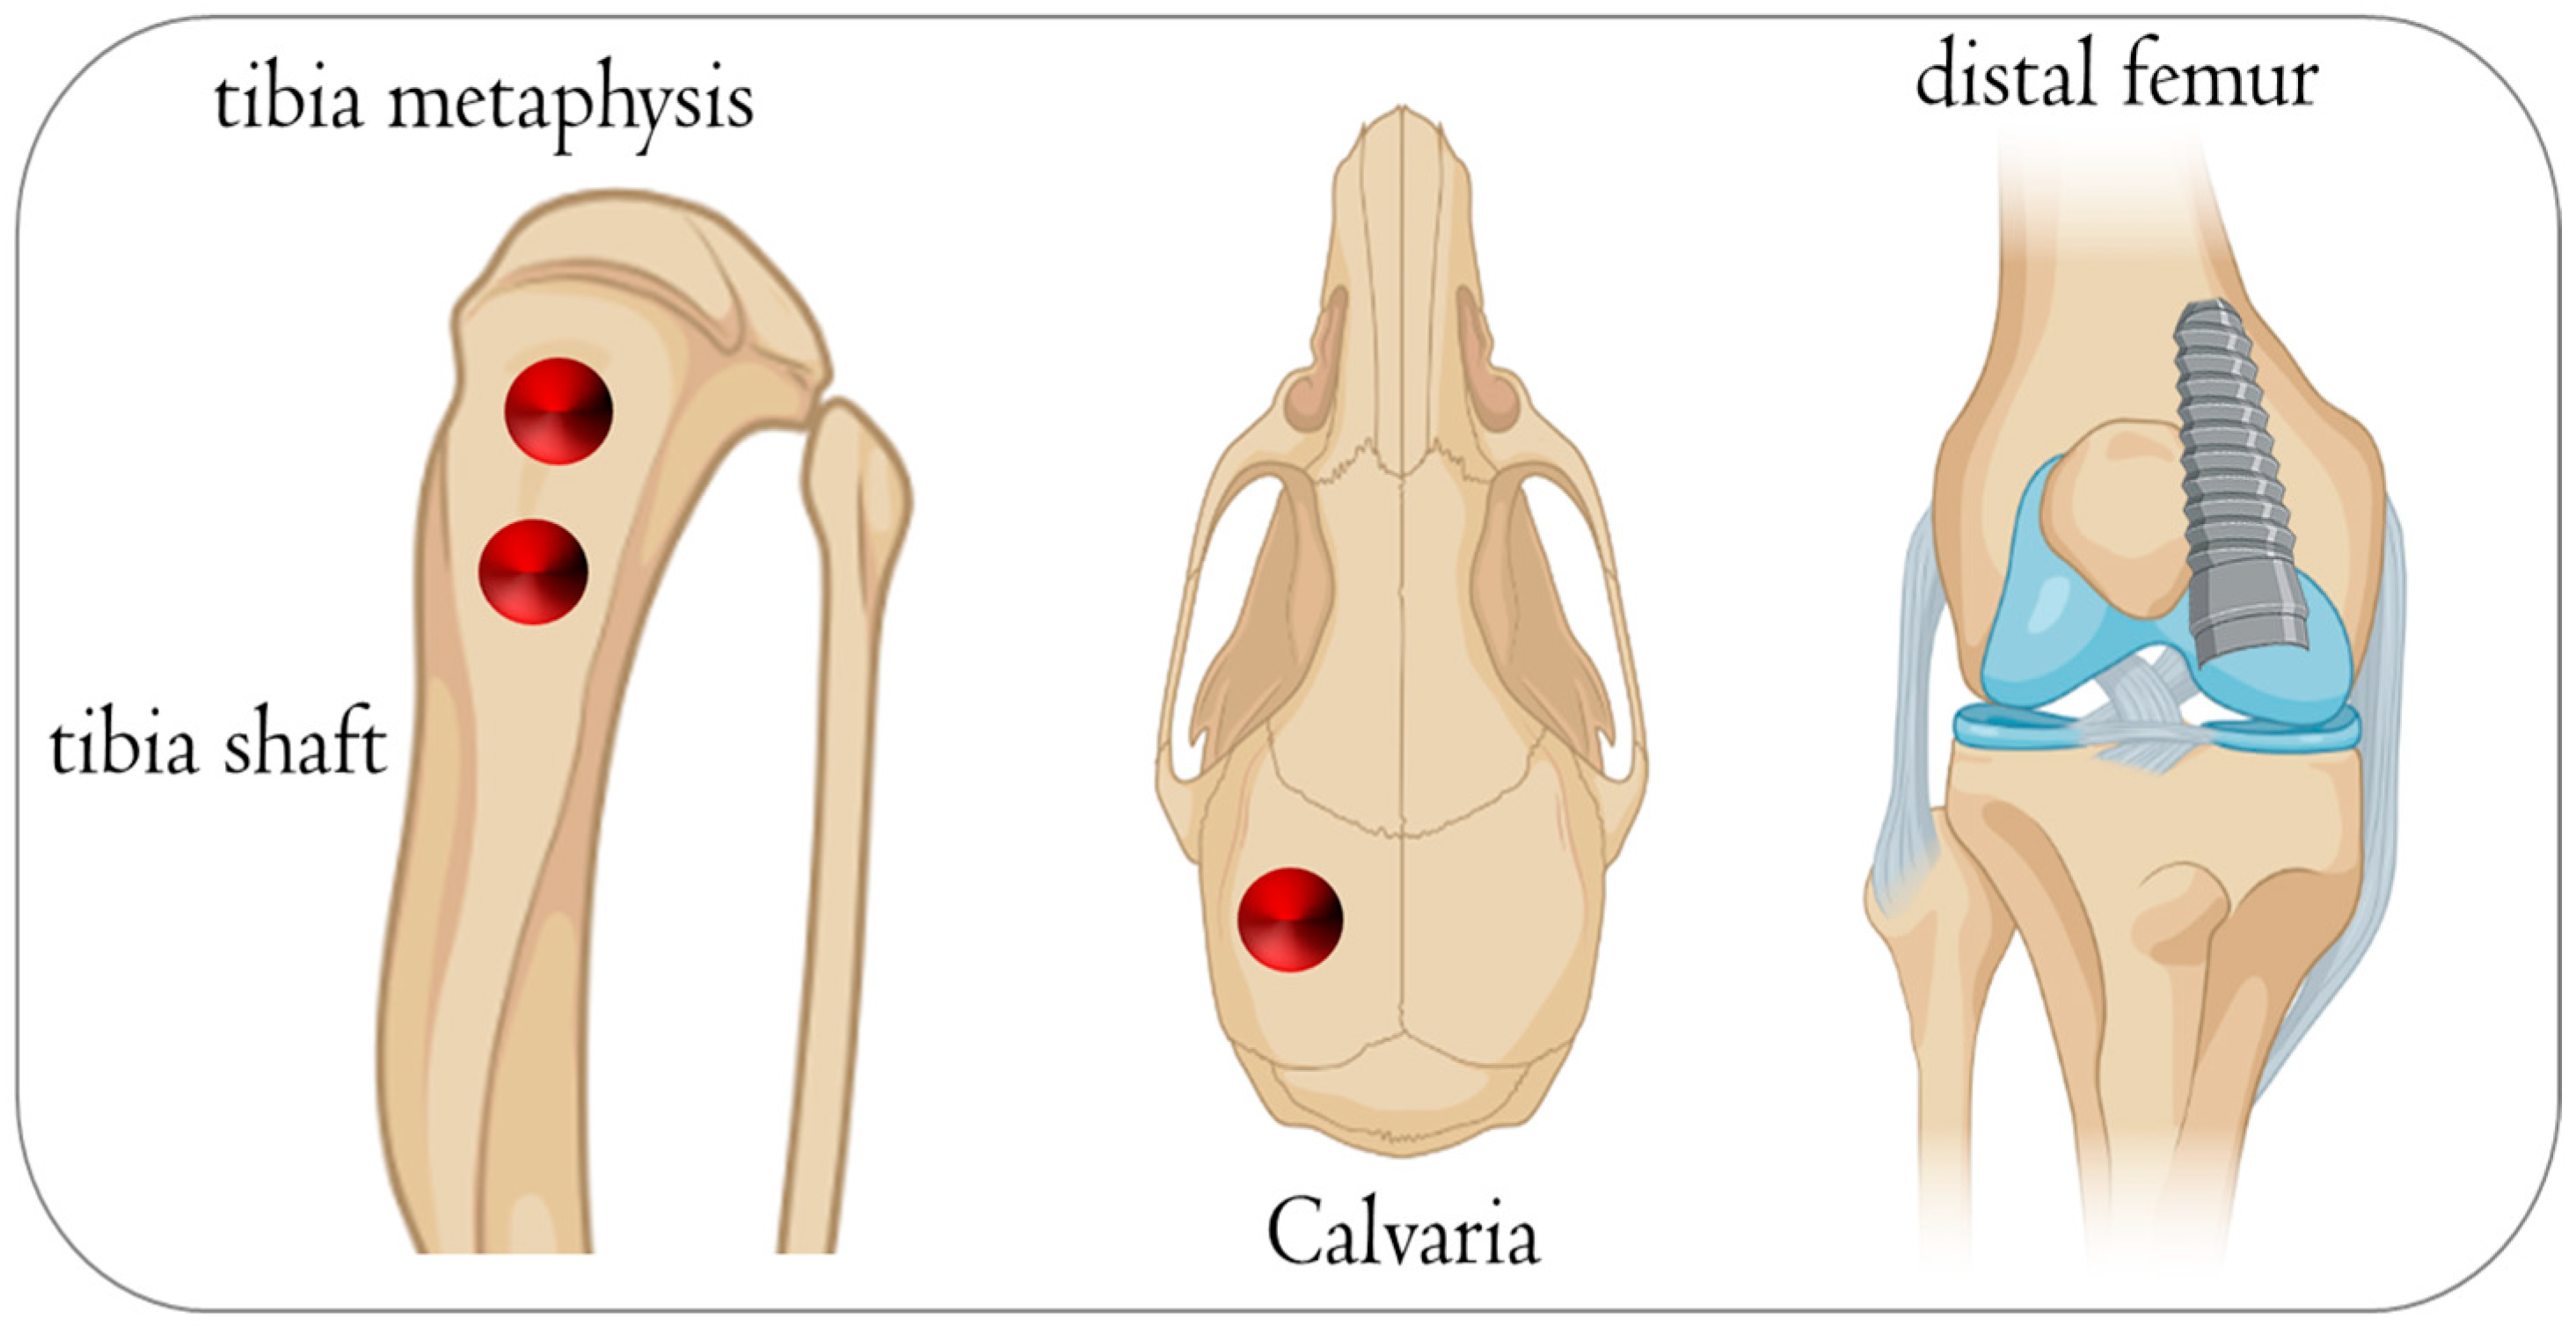

3.2. Rabbit

- Scarano, A.; Piattelli, A.; Quaranta, A.; Lorusso, F. Bone Response to Two Dental Implants with Different Sandblasted/Acid-Etched Implant Surfaces: A Histological and Histomorphometrical Study in Rabbits. BioMed Res. Int. 2017, 2017, 8724951. [Google Scholar] [CrossRef]

- Scarano, A.; Inchingolo, F.; Rapone, B.; Lucchina, A.G.; Qorri, E.; Lorusso, F. Role of Autologous Platelet Gel (APG) in Bone Healing: A Rabbit Study. Appl. Sci. 2021, 11, 395. [Google Scholar] [CrossRef]